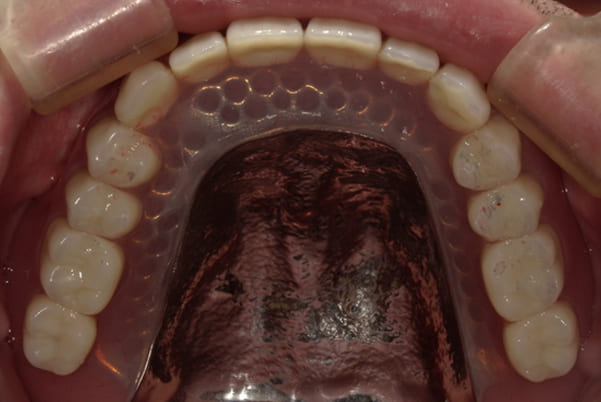

-

上顎治療後

下顎治療後